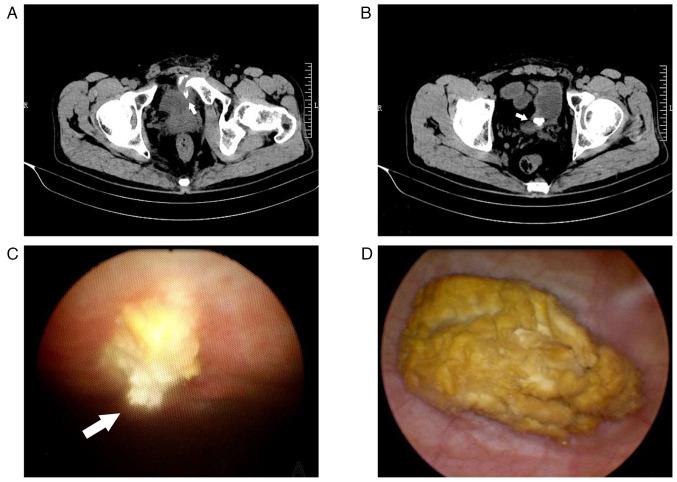

Pelvic fractures sometimes lead to injuries of the urinary bladder, which commonly present as gross hematuria, dysuria and lower abdominal pain. As a type of urinary stone, bladder stones are usually secondary to lower urinary tract obstruction, such as benign prostatic hyperplasia, urethral stricture, and neurogenic bladder. The present case report examines an unusual case of a delayed pubic fracture penetrating the bladder, which caused a secondary bladder stone. A 53-year-old man was first hospitalized at The Second Hospital of Jiaxing (Jiaxing, China) in January 2020 because of trauma-induced bleeding in the scalp and abdominal pain. The patient underwent abdominal exploration and partial bowel resection, and his condition stabilized after surgery. After discharge, the patient had regular outpatient check-ups every 2-3 weeks. However, after 3 months, in April 2020, the patient was readmitted to the hospital because of frequent urination, an urgent need for urination and dysuria. Abdominal computed tomography imaging and cystoscopy revealed a pubic fracture that had penetrated the bladder wall, accompanied by a bladder stone. Subsequently, cystolithotomy was performed, which provided significant relief of symptoms once the catheter was removed after 2 weeks. Since then, the patient has been followed up until January 2023 and had remained asymptomatic. Bladder stones caused by necrotic bone fragmentation are rare. Bladder injuries resulting from pelvic fractures can have delayed onset; therefore, clinicians should be aware of the possibility of urogenital injury in such patients. It is crucial for clinicians to comprehend the potential mechanisms involved, analyze the clinical data of patients, closely monitor their condition and implement appropriate treatment measures when necessary.

骨盆骨折有时会导致膀胱损伤,通常表现为肉眼血尿、排尿困难和下腹部疼痛。膀胱结石作为泌尿系统结石的一种,通常继发于下尿路梗阻,如良性前列腺增生、尿道狭窄和神经源性膀胱。本病例报告研究了一例罕见的耻骨骨折延迟穿透膀胱导致继发性膀胱结石的病例。一名53岁男性于2020年1月因创伤性头皮出血和腹痛首次入住嘉兴市第二医院(中国嘉兴)。患者接受了腹部探查和部分肠切除术,术后病情稳定。出院后,患者每2 - 3周进行一次定期门诊检查。然而,3个月后的2020年4月,患者因尿频、尿急和排尿困难再次入院。腹部计算机断层扫描成像和膀胱镜检查显示耻骨骨折穿透膀胱壁,并伴有膀胱结石。随后进行了膀胱切开取石术,术后2周拔除导尿管后症状明显缓解。此后,对患者进行随访直至2023年1月,患者一直无症状。由坏死骨碎片引起的膀胱结石很少见。骨盆骨折导致的膀胱损伤可能会延迟出现;因此,临床医生应意识到此类患者存在泌尿生殖系统损伤的可能性。临床医生理解其中潜在机制、分析患者临床数据、密切监测病情并在必要时采取适当治疗措施至关重要。